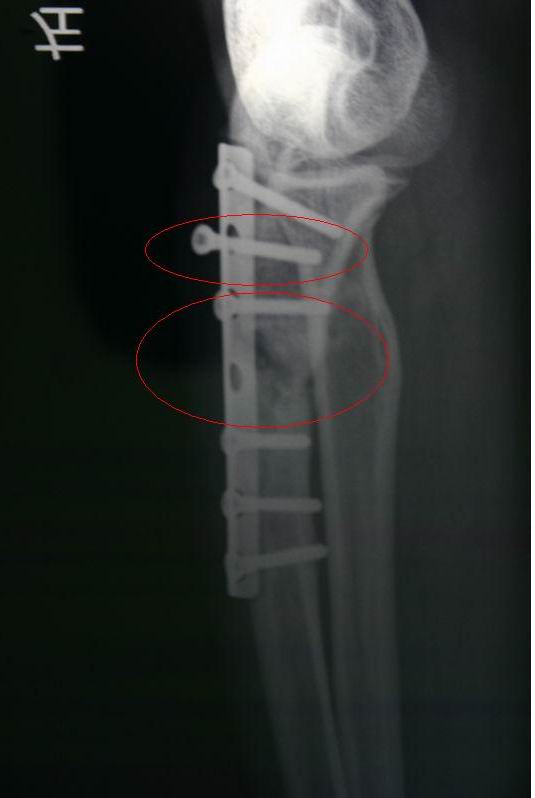

前年十月骨折,镶了钢板,手术7个月后跑西藏,现在有点移位,一颗锣丝松了。。骨头现在还没长好。。再长不好又要开刀。。现有什么玩意能帮忙骨头快速生长。谢谢